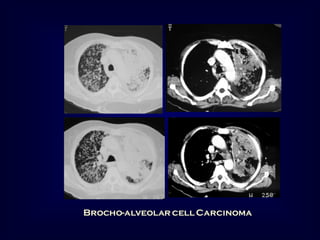

Bronchoalveolar carcinoma

Other causes: Lymphoma,

pulmonary edema, some

types

of

pneumonia

[obstructive, lipoid]

6-10% of primary lung cancer

Cough, sputum, weight loss, hemoptysis, bronchorrhea

Radiographic patterns :

Single or multiple pulmonary nodules [ Air bronchogram]

Segmental or lobar consolidation.

Diffuse air space disease .

CT angiogram (non specific)

Visualization of

pulmonary vessels

within airless lung

Alveolar cell Carcinoma

Broncho aleveolar carcinoma

Brocho-alveolar cell Carcinoma